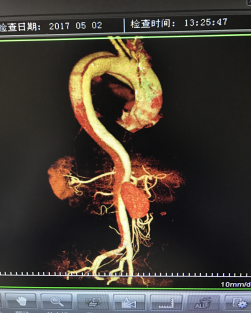

5月2號劉大伯照常早起干活,突然胸部劇烈疼痛,難以忍受,全身大汗,同時伴有右上肢發(fā)涼,他心想這次心絞痛比之前嚴重的多啊,趕緊叫上孩子到吉林國文醫(yī)院心血管內科住院,患者長期高血壓病史,血壓一直控制不理想,大夫給他做了檢查,測左上肢血壓:82/45mmHg,右上肢血壓測不出,心率52次/分,右側肱動脈、尺動脈、橈動脈搏動消失,左側股動脈搏動較右側弱。“糟了,雙側血壓差別這么大,是不是主動脈夾層了?”,接診大夫趕緊找來李主任,李主任反復詢問患者病情,表情突然凝重起來,患者胸痛這么明顯,血壓低的厲害,主動脈夾層的可能性很大。二話不說,李主任立即聯系影像科的醫(yī)生準備做主動脈CTA,移動患者做檢查的過程大夫們非常小心,嚴密監(jiān)測患者血壓變化情況。兩個小時后結果出來了,主動脈夾層從升主動脈一直撕裂到左側髂總動脈?。?!

從開始學醫(yī)到現在已經快9年了,主動脈夾層患者也見過一些,但像劉大伯這種危險類型的還是第一次見到,心里真的為他捏把汗,撕裂的主動脈隨時都有可能破裂,生命隨時可能終止,要知道主動脈夾層的死亡率非常的高,約50%的患者發(fā)病后48小時死亡,約90%的患者發(fā)病1個月內死亡。

李主任詳細的與劉大伯的女兒交代了病情,手術是挽救生命的唯一辦法,為了劉大伯的一線生機,我們積極聯系了我省權威的心血管外科,并做了詳細的匯報,兩家醫(yī)院對此非常重視,為劉大伯開通了綠色通道,安全的把他總到上級醫(yī)院,當天便給他進行血管置換及覆膜支架植術。他術后恢復的很好,后來劉大伯的女兒看望我們,感嘆道:沒想到國文醫(yī)院心內科應急能力這么高,在那么短的時間內診斷明確,才給了我的老父親手術的機會。